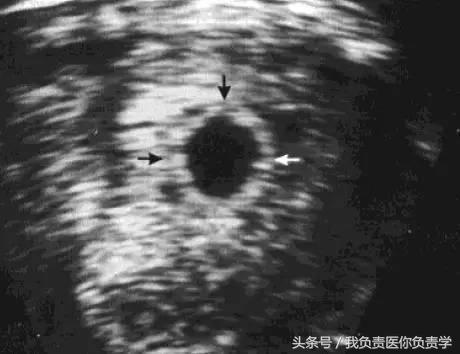

箭头所指为妊娠囊,呈「双环征」,内层为强回声环,外层为低回声环